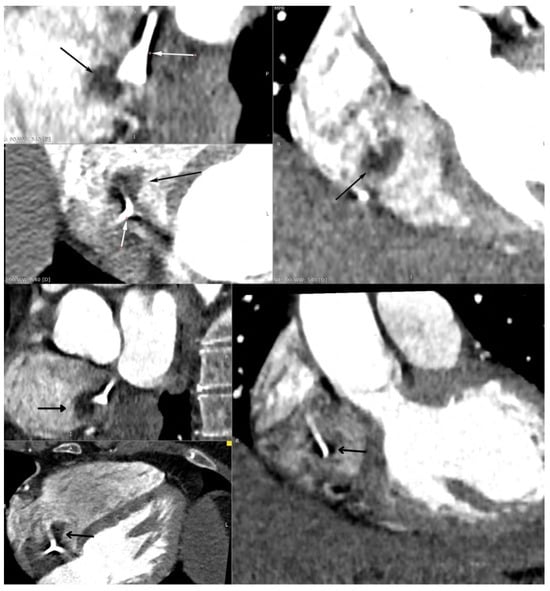

Echocardiography remains a vital part of the initial assessment and monitoring of oncological patients. It allows for proper treatment selection but can also reveal life-threatening complications, including impaired left ventricular function or thromboembolism. It can rarely detect intracardiac masses that require further investigation. In the presented case, a 51-year-old female patient with left-sided breast cancer, who had undergone neoadjuvant chemotherapy, was hospitalised due to a right atrial mass identified via routine transthoracic echocardiography (TTE). Initial anticoagulation therapy showed no clinical improvement. Follow-up TTE revealed a 12 × 19 mm hyperechogenic, mobile mass in the right atrium (RA). Computed tomography angiography (CTA) ruled out pulmonary embolism and revealed that the mass was located close to the tip of the vascular access port. Transoesophageal echocardiography showed that the lesion was not connected to the vascular port. Based on location and mobility, the lesion was most consistent with a cardiac myxoma. After the Heart Team made a decision, endovascular intervention using a vacuum-assisted device was performed without complications. Histopathological examination excluded thrombosis and myxoma, revealing a fibro-inflammatory lesion. A multimodality approach is necessary to assess RA masses. However, even an extensive evaluation could be misleading, so treatment options should always be subject to the Heart Team’s decision. Full article

Figure 1